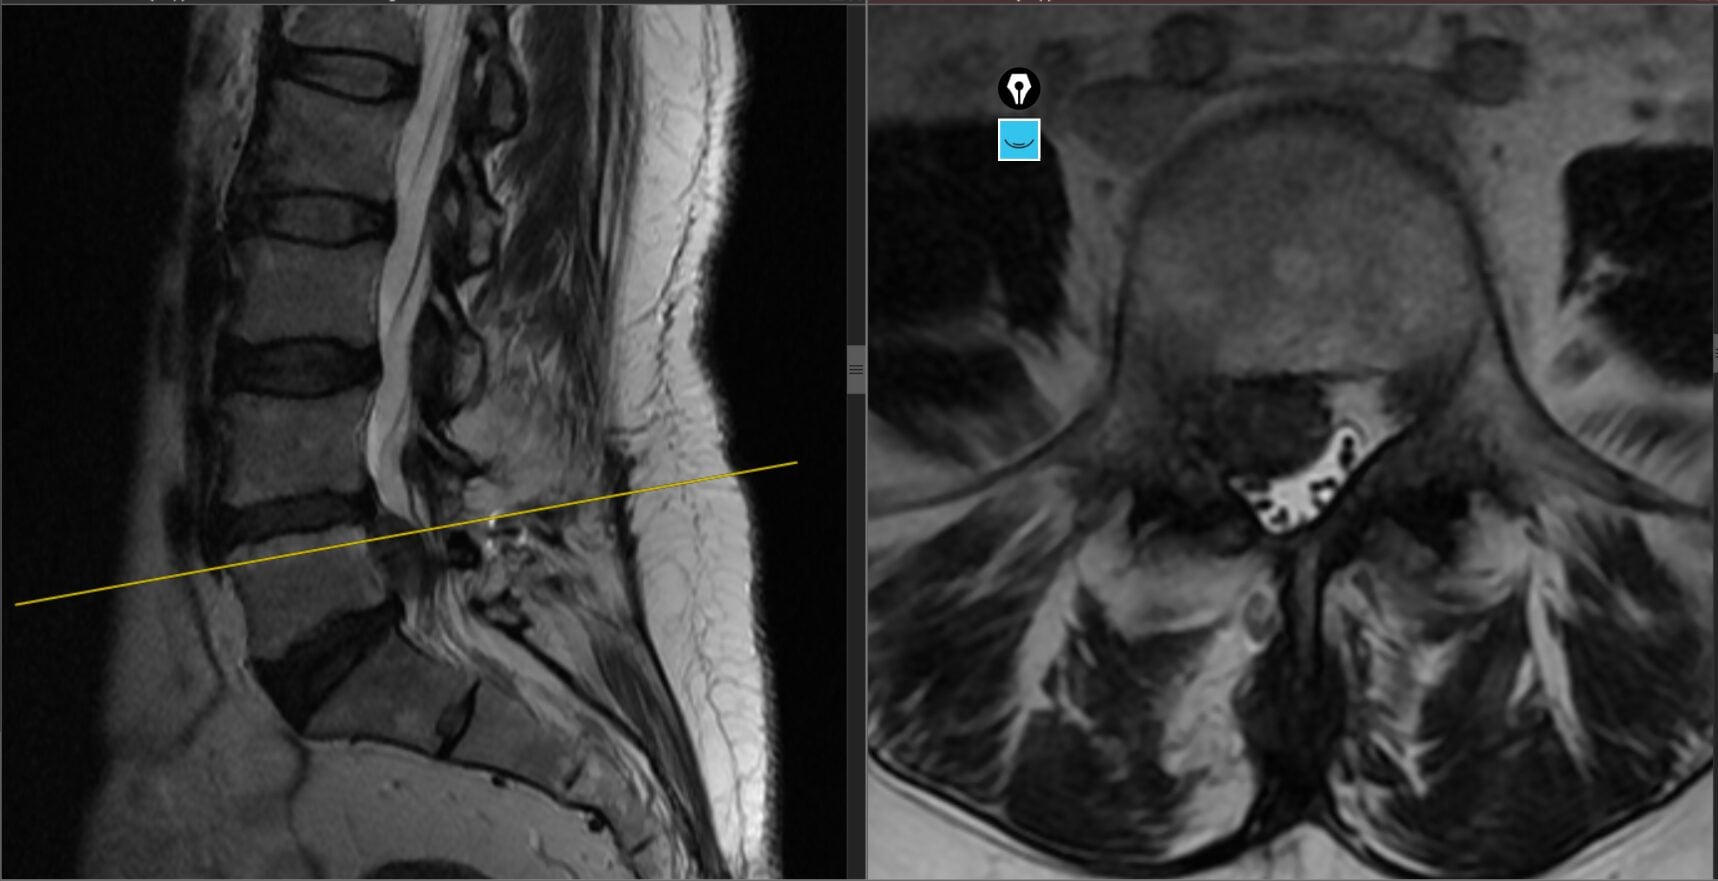

Studiu de caz: Hernie de hisc lombară recidivată L4–L5 tratată prin chirurgie ULTRA laterală minim invazivă – Caz din București, tratat la ANSI Constanța

Hernia de disc lombară recidivată este o cauză frecventă de durere persistentă după intervenții chirurgicale ale coloanei. Acest caz evidențiază beneficiile unei abordări moderne, minim invazive, în tratamentul acestei patologii complexe. Contextul pacientului Pacientul este un bărbat activ, în vârstă de 35 de ani, din București, cu antecedente de intervenție chirurgicală lombară. Deși inițial a […]